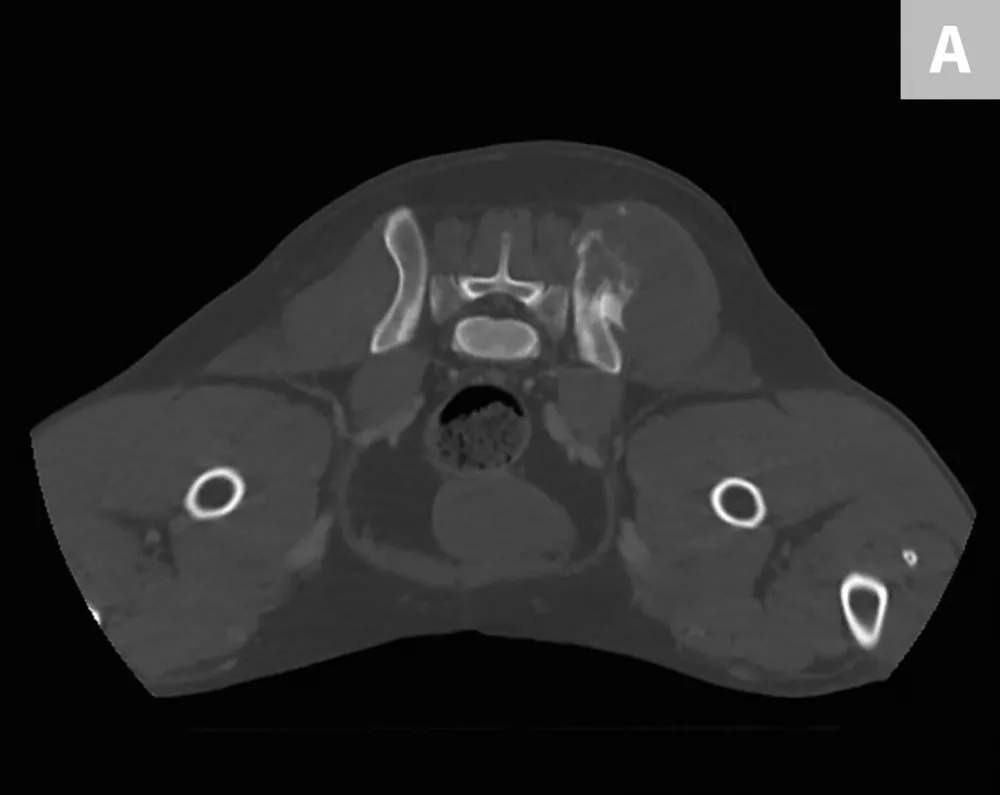

Featured Image

FIGURE 2

Axial CT images showing a large mass arising from the right ilium with a significant soft-tissue component in both the inner and outer tables of the pelvis

Because the lungs are the most common site of metastasis in cases of chondrosarcoma, staging was determined via bone scan and chest CT, which confirmed that there were no other sites of disease. Staging was determined to be Enneking Stage IB; prognosis was good overall. Core needle biopsy confirmed low-grade chondrosarcoma.